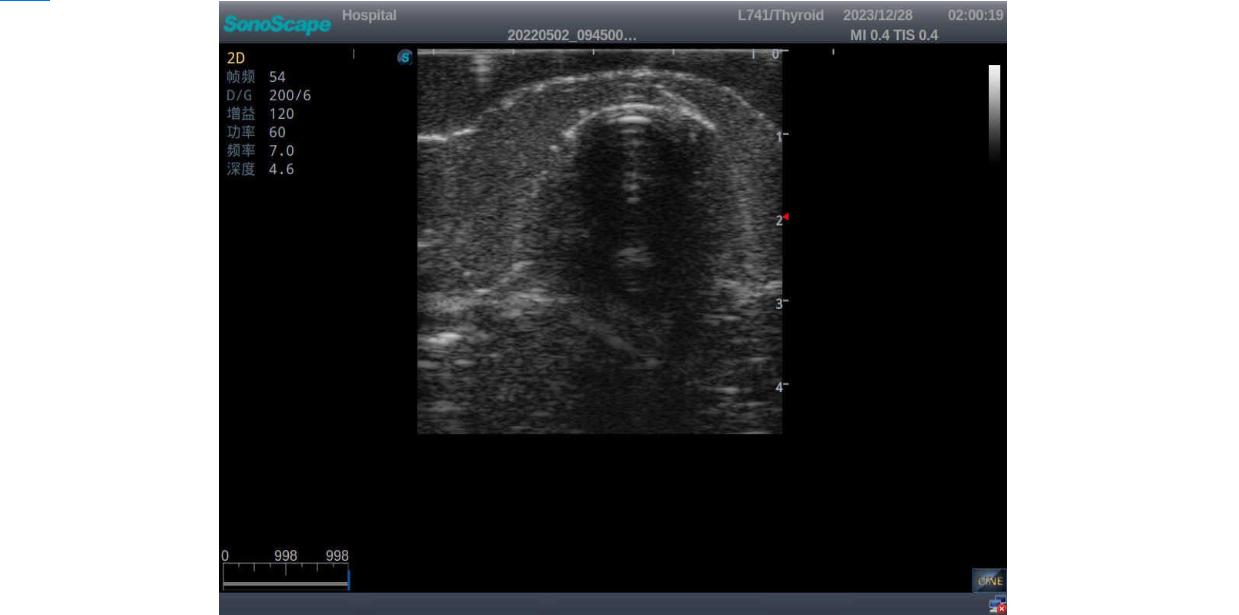

3)       It comes with four (4) thyroid modules and can show five (5) ultrasonic images: normal thyroid, thyroid adenoma, thyroid cancer, nodular goiter, thyroid cyst

Thyroid adenoma with well-defined border and smooth uniform halo